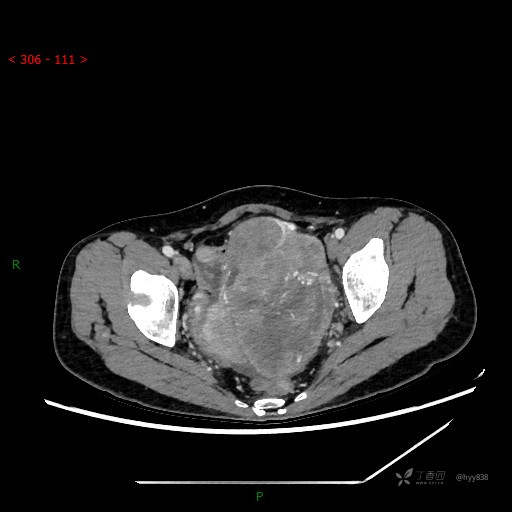

辅助检查:CT

盆腔CT平扫

增强动脉期

静脉期